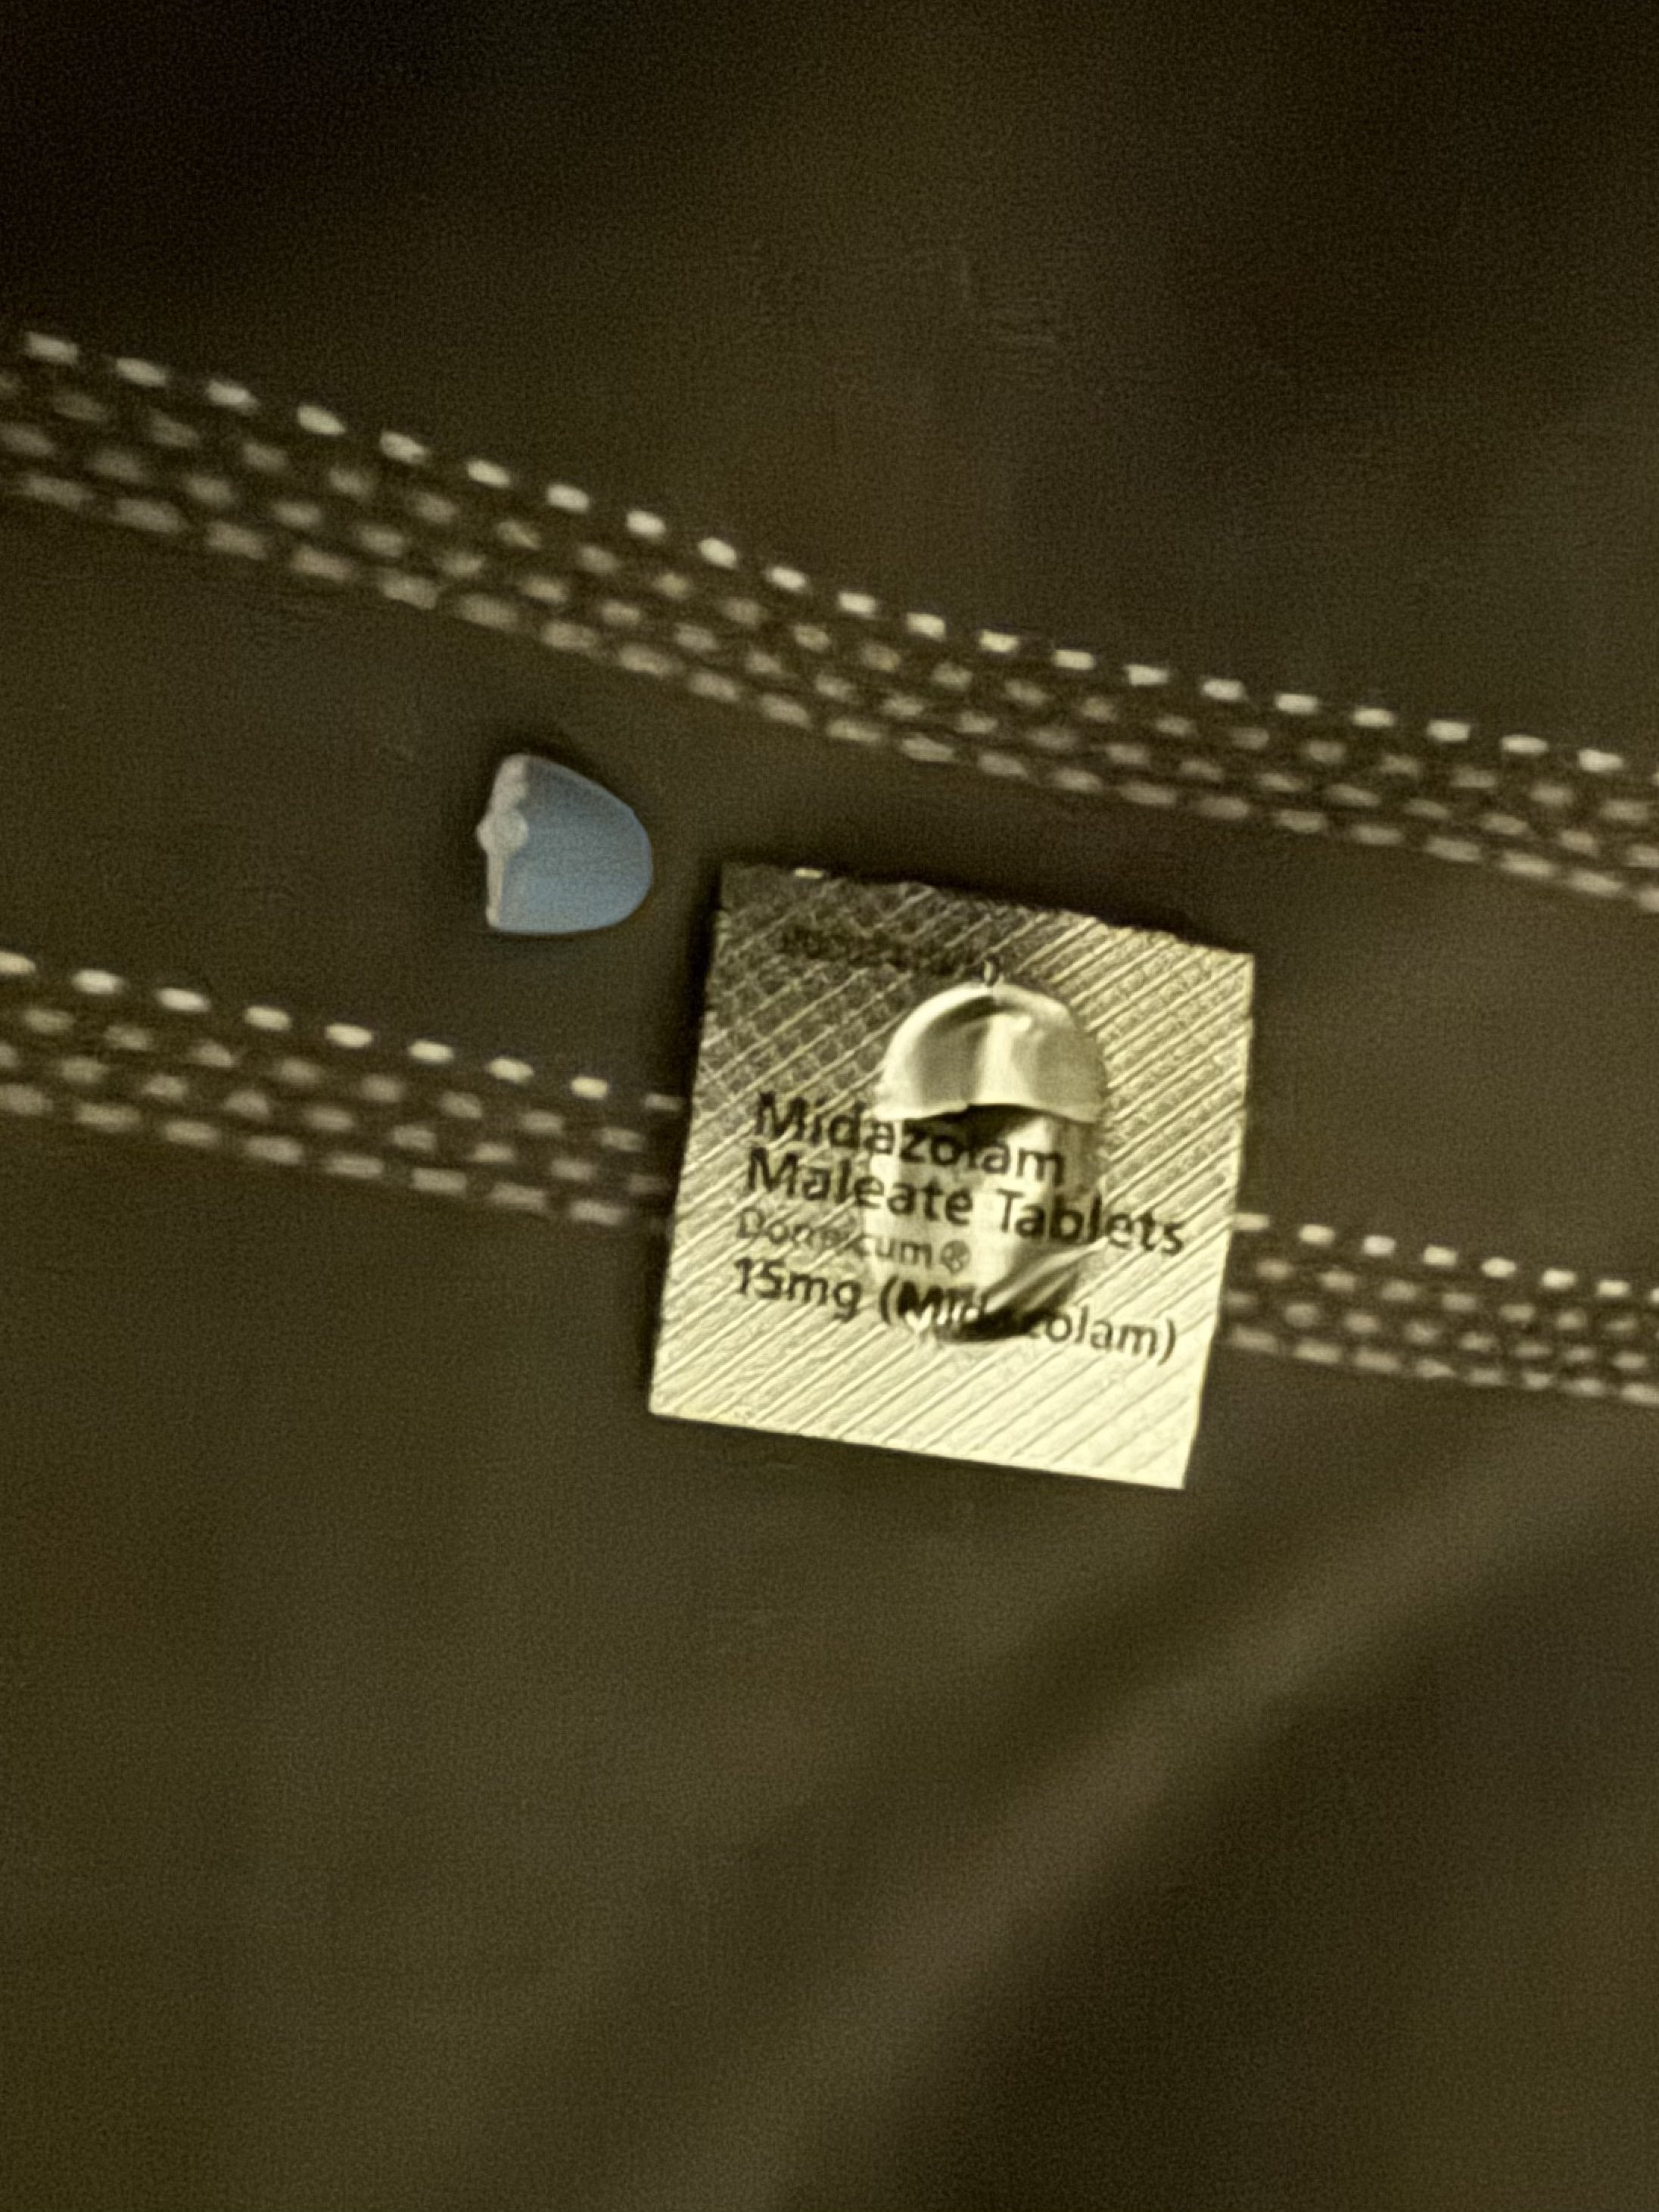

对于药物过量引起的中枢神经系统副作用,有一些不常见或常见的药物来控制症状。

评论区欢迎补充 https://t.co/7S4tGVDEM5

炽烈已极 @AnIncandescence@_mucha_000 bzd太多了而且大家好像都知道可以用?我看看有没有特别侧重某些效果的bzd

炽烈已极 @AnIncandescence苯二氮卓类药物:镇静作用。bzd通过提高内源性化学物质GABA的有效性来降低神经元的兴奋性。 https://t.co/Z1mc5JJGrg